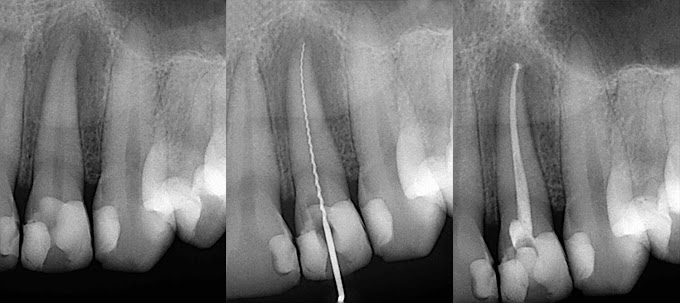

Read moreInside every tooth is delicate tissue called, "the mash", which goe…